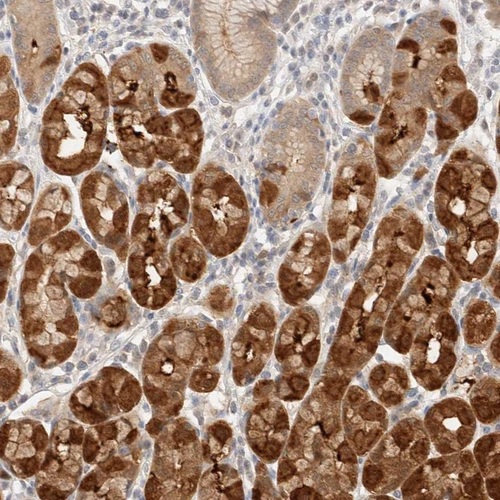

Immunohistochemical staining of human rectum shows moderate cytoplasmic positivity in glandular cells.